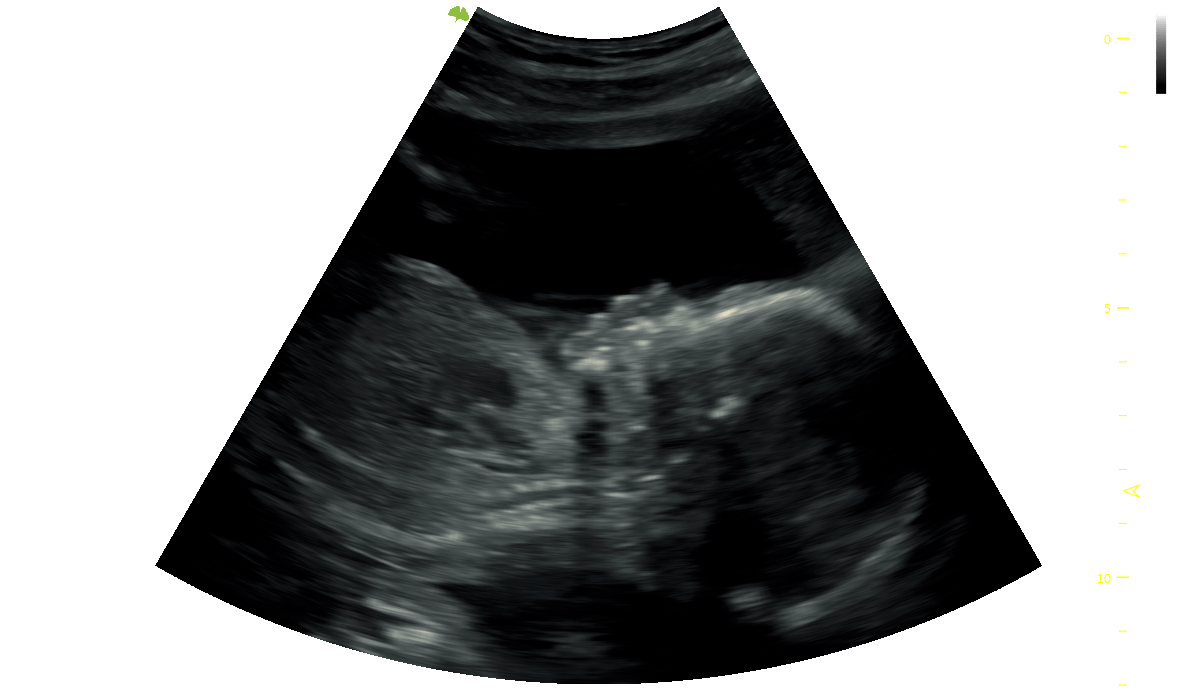

This scan is recommended around 28 weeks and includes reassurance by assessing the viability and wellbeing of your baby, hearing the heartbeat, growth measurements providing an estimated fetal weight and viewing baby in 3D, 4D and now 5D with Samsung’s exclusive patented software technology.

Our entry-level 5D bonding scan is available from 20 weeks with the optimum time around 28 weeks with no cut-off point, this scan includes basic well-being checks of your baby, hearing the heartbeat and viewing baby in 5D with Samsung's exclusive patented software technology. With our wall-mounted HD/5D flat-screen television and family-sized sofa, everyone will be able to enjoy the experience.